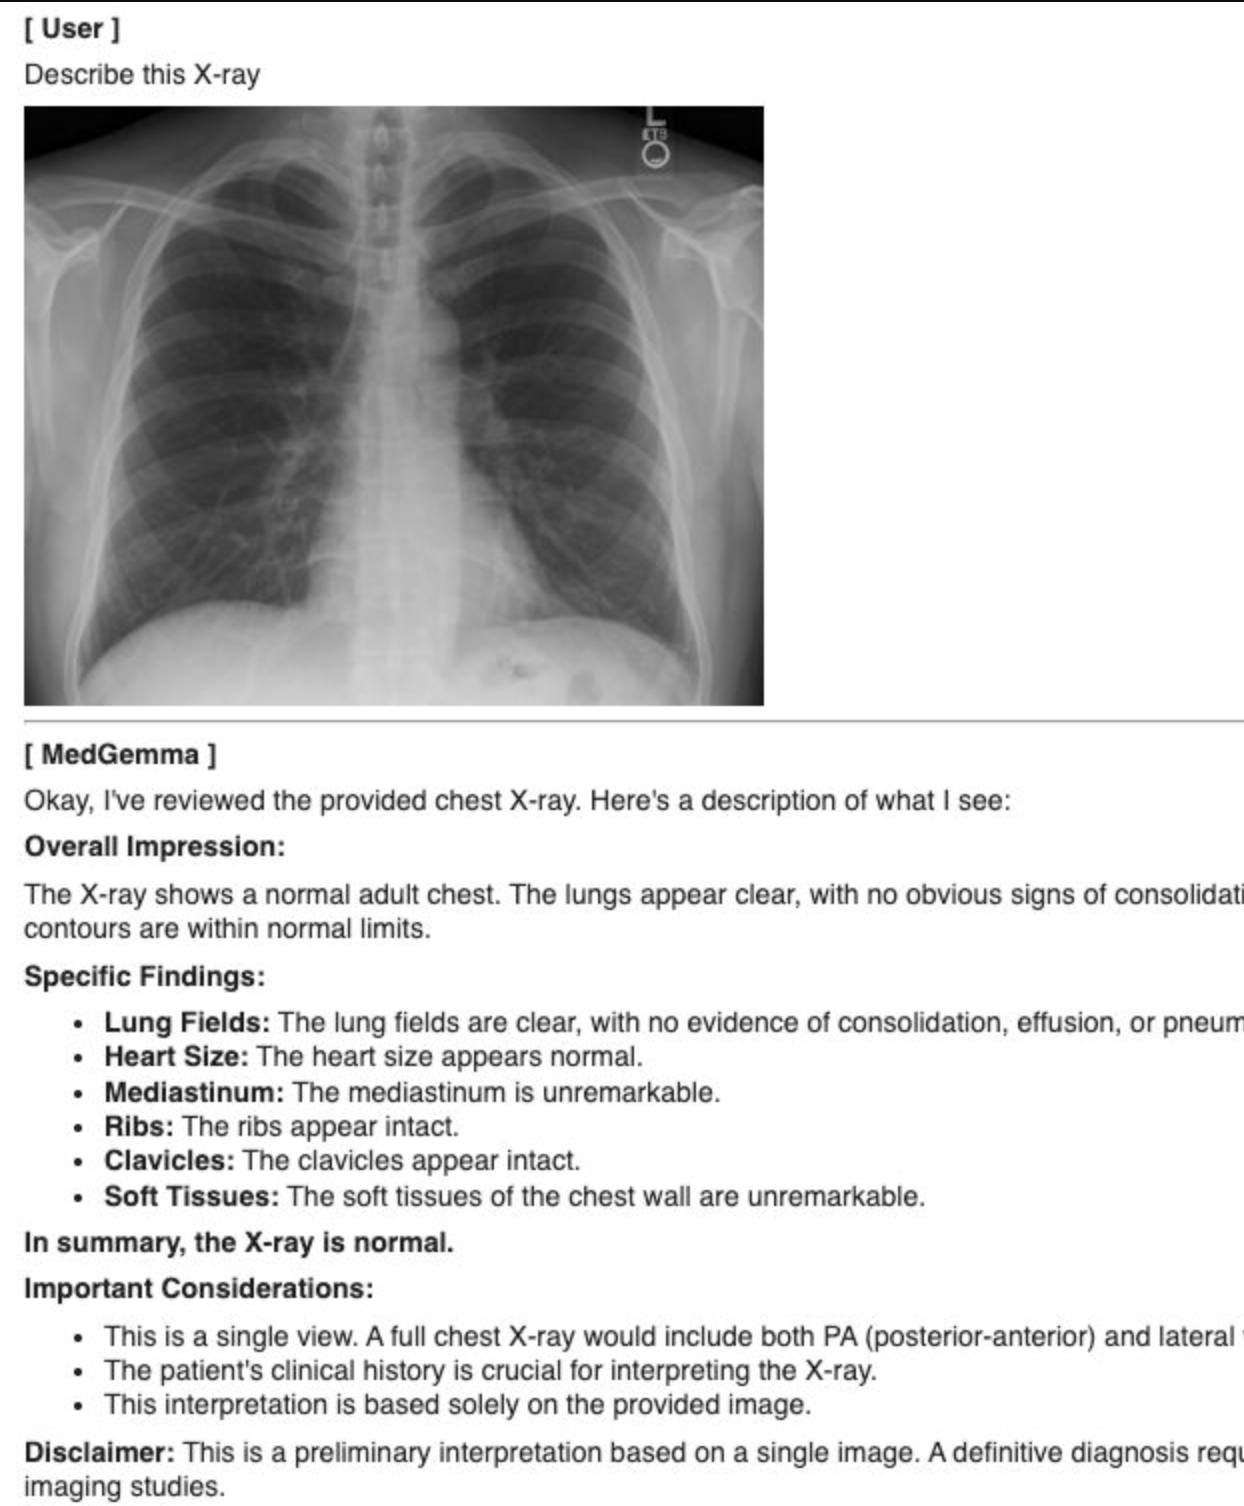

7. MedGemma 3n: 의료용 Ai

근데 바로 이 모델을 활용해서 의료용 AI가 전 세계에 무료로 풀려버렸다. 바로 메드젬마... '전 세계 의사들아, 다 와서 붙어라! 공짜다!' 라고 쓰고, '너희 지능을 공짜로 내게 바쳐라!' 라고 읽는다. 엑스레이 분류, MRI, CT 영상 해석, 의학 텍스트 이해와 임상적 추론, 환자 인터뷰, 분류, 임상 의사 결정 지원 등에 사용할 수 있는 모델이다.